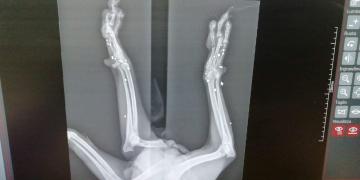

LIBERO Era solo un cucciolo….!!! Gli avevano sparato!! Fu trovato sofferente che zoppicava, nella periferia di Palermo, laddove abbandonano i cani non desiderati. FORSE LIBERO ERA RIUSCITO A SCAPPARE PRIMA CHE IL SUO CARNEFICE LO FINESSE Qualcuno si era divertito a sparare alle sue zampette.. Un cucciolo … come si puo’ fare questo ad un esserino innocente?

Adesso Libero si trova ancora in Sicilia in provincia di Palermo. Sono già passati 6 anni e per lui nessuno ha mai chiamato.. RIPROVIAMOCI.. Libero ha una zampetta impallinata che ha frantumato le ossa. Purtroppo non si puo’ intervenire chirurgicamente e cio’ gli impedisce di poggiarla in terra, ma questo non fa di lui un cane non autosufficiente. Libero è un cane dolcissimo di taglia medio piccola, bellissimo, timido con gli altri cani e si sottomette a loro,povero tesoro. Corre e gioca normalmente. Castrato e vaccinato e soprattutto negativo alla Leishmania.